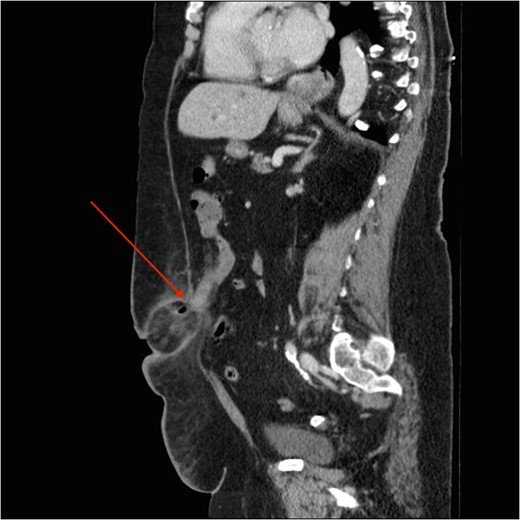

Sagittal slice of the CT demonstrating the paraumbilical sac containing cecum and appendix along with fat stranding and air loculation and narrow neck (red arrow).